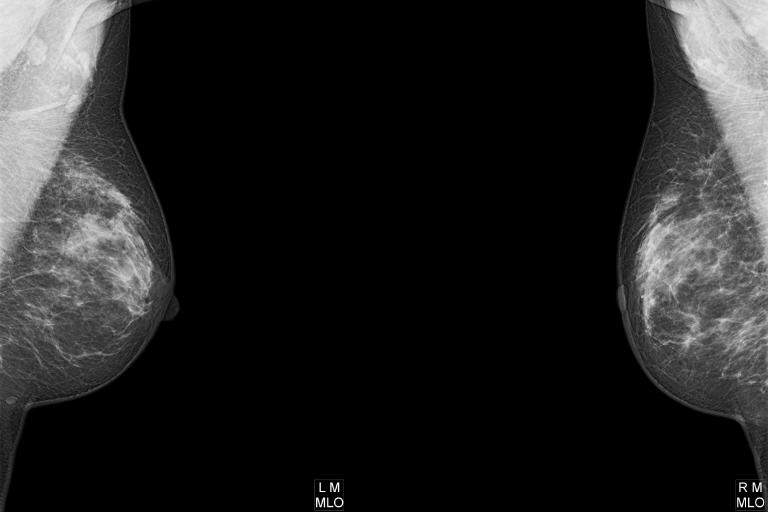

Die Mammographie ist eine spezielle Röntgenuntersuchung der Brust, die dazu dient, Veränderungen im Brustgewebe, wie z. B. Knoten oder Verkalkungen, frühzeitig zu erkennen. Dabei wird die Brust zwischen zwei Platten kurz zusammengedrückt, um klare Bilder zu erhalten. Der Vorgang kann etwas unangenehm sein, dauert aber nur wenige Minuten. Die Mammographie ist eine wichtige Methode zur Früherkennung von Brustkrebs und hilft, bereits kleinste Veränderungen festzustellen, bevor sie tastbar sind.

Die Mammatomosynthese, auch 3D-Mammographie genannt, ist eine weiterentwickelte Form der Mammographie. Dabei werden aus verschiedenen Winkeln mehrere Röntgenaufnahmen der Brust gemacht, die dann zu einem dreidimensionalen Bild zusammengesetzt werden. Dies ermöglicht eine noch genauere Untersuchung des Brustgewebes und erleichtert es, kleine Veränderungen oder Tumore zu erkennen, die in einer herkömmlichen Mammographie möglicherweise übersehen würden. Der Ablauf ist ähnlich wie bei der normalen Mammographie und dauert nur wenige Minuten.